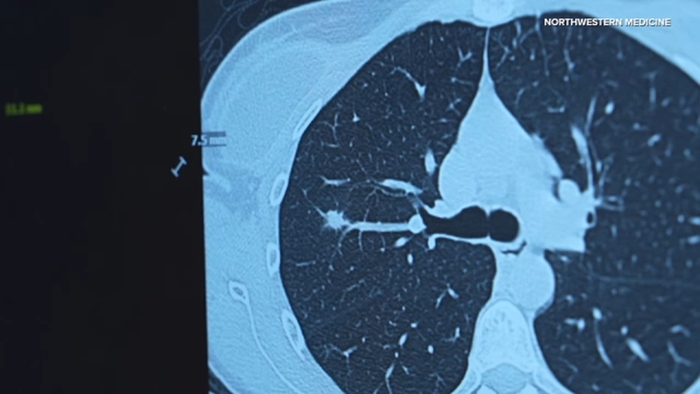

Chicago study pushes for expanded lung cancer screenings

Northwestern Medicine is launching a new lung health center to help detect lung cancer at earlier ages. This comes after a new study shows the cancer is impacting young women and non-smokers.